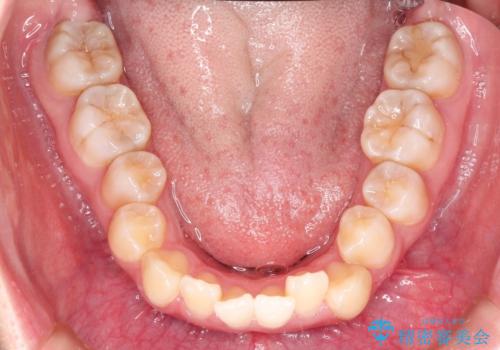

- 前歯のガタガタと、かみ合わせを改善したいとのことで来院されました。

下顎の歯が、上顎の歯に対して前方に位置していたので、下顎の歯を後方に移動させるのと、歯と歯の間を削りスペースを作り、歯を並べる計画としました。